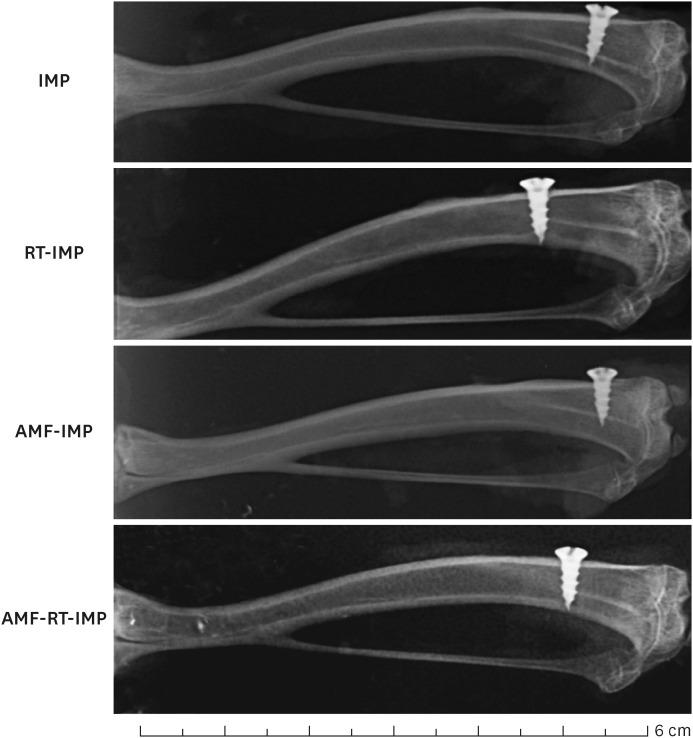

Thirty-five adult male Wistar rats were randomly divided into one healthy and four experimental groups. In three consecutive days, two experimental groups of rats (AMF-RT-IMP and RT-IMP) were exposed to radiation (15 Gy/3 fractions of 5 Gy each). Then the titanium implants were inserted into the left tibia. Before the radiotherapy process, a 200 mg/kg dose of amifostine (AMF) was administered to the rats in the AMF-IMP and AMF-RT-IMP groups. Twenty-eight days after the screw implant, all rats were sacrificed, and their blood samples and tibia bones were collected for analysis.

The results indicated an accelerated bone formation and a more rapid healing process in the screw implants in the AMF-IMP, AMF-RT-IMP, and AMF-RT groups than in the RT-IMP group. Also, bone-implant contact area measurement and inflammation decreased with amifostine treatment in the implants subjected to irradiation ( < 0.05).

方法

结果